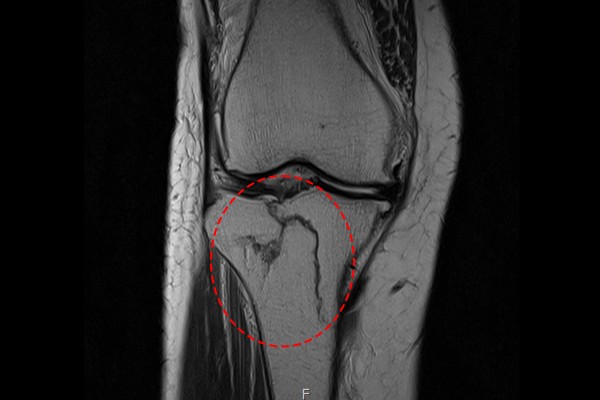

환자분께서는 내원해주실 때 타병원에서 촬영하신 MRI를 지참해오셨습니다. MRI 사진을 확인해보니 증상을 호소하신 무릎 경골 고평부에서 명확한 골절 확인되었습니다.

2f992d7239a97edca630fa072198310c_1766717638_0021.jpg

측면 MRI 사진에서 역시 명확하게 골절선이 확인되어 무릎 경골 고평부 골절(Fx. tibia plateau knee Rt.[Schatzker 4 or 5])을 진단하였습니다.